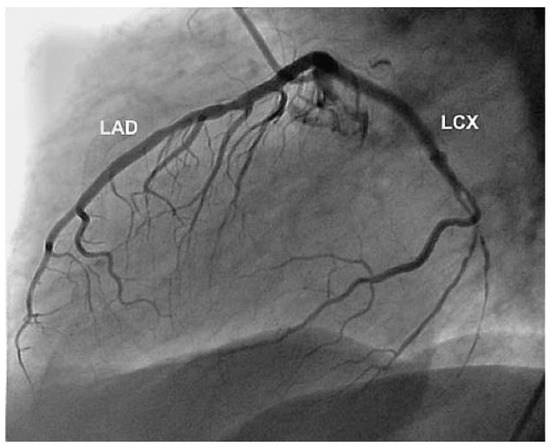

Aneurysm of the Left Circumflex Coronary Artery

by Christian Arranto, Christoph Auf der Maur and Paul Erne

Cardiovasc. Med. 2010, 13(7), 247; https://doi.org/10.4414/cvm.2010.01511 - 11 Aug 2010

Viewed by 66

Abstract

A 54-year-old man was hospitalised because of an inferior ST-elevation myocardial infarction [..] Full article

Show Figures

Figure 1